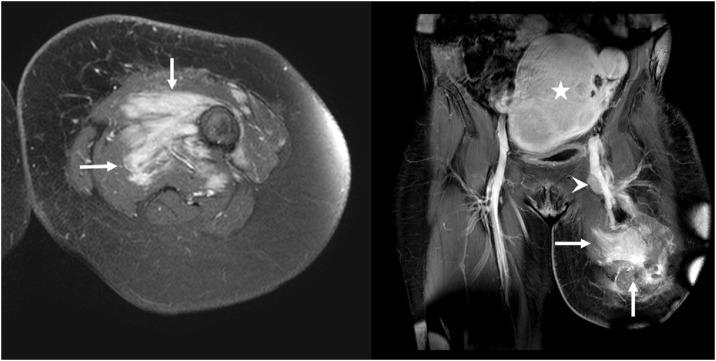

Diffuse-type tenosynovial giant cell tumor (D-TGCT), otherwise known as pigmented villonodular synovitis, is a locally aggressive tumor which can show multiple recurrences but is rarely associated with metastasis. A handful of studies have elucidated the imaging features and clinical course in metastatic D-TGCT with malignant transformation on histology. However, only 5 cases of metastatic D-TGCT with benign histological features have been reported in the literature, with the clinical course and prognosis reported in only 1 case. Therefore, relatively little is known about the implications of histologically benign metastasis on the role of imaging, management, and clinical outcomes. We report a case of a 51-year-old female with recurrent D-TGCT localized to the knee that metastasized to the lymph nodes and soft tissue 3 years after above-the-knee amputation and 16 years after initial diagnosis of localized D-TGCT, despite benign histologic features on lymph node excision. This case highlights the necessity of timely MRI imaging to prevent delayed diagnosis, the role of histological findings on treatment response, and clinical outcomes associated with metastasized D-TGCT.

弥漫型腱鞘巨细胞瘤(D-TGCT),又称色素沉着绒毛结节性滑膜炎,是一种具有局部侵袭性的肿瘤,可多次复发,但很少发生转移。少数研究阐述了组织学上发生恶性转化的转移性D-TGCT的影像学特征和临床病程。然而,文献中仅报道了5例组织学特征为良性的转移性D-TGCT,其中仅1例报道了临床病程和预后。因此,对于组织学上良性转移对影像学作用、治疗及临床结局的影响,人们了解相对较少。我们报告了一例51岁女性,患有复发性D-TGCT,病变局限于膝关节,在膝上截肢3年后及初次诊断局限性D-TGCT 16年后转移至淋巴结和软组织,尽管淋巴结切除的组织学特征为良性。该病例强调了及时进行MRI成像以防止延迟诊断的必要性、组织学结果对治疗反应的作用以及与转移性D-TGCT相关的临床结局。